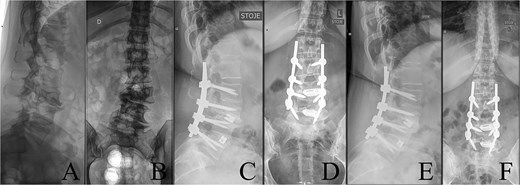

Last preoperative X-ray, lateral (A) and anteroposterior view (B). After 10 weeks of follow-up; lateral (C) and anteroposterior view (D). After 1 year of follow-up; lateral (E) and anteroposterior view (F).

The postoperative course was uneventful, with no evidence of neurological dysfunction. The patient commenced physiotherapy on the first postoperative day. At the initial follow-up, 10 weeks post-surgery, she was ambulating unassisted with reduced back and leg pain, without neurological impairment but with a persistent forward-leaning posture that remained correctable with verbal cues. At the final follow-up, one year after surgery, she reported resurgence of forward-leaning posture after longer walks, and referred to a tertiary rehabilitation institution. Imaging demonstrated L2–L5 fusion with no signs of instability or residual deformity (Fig. 1).